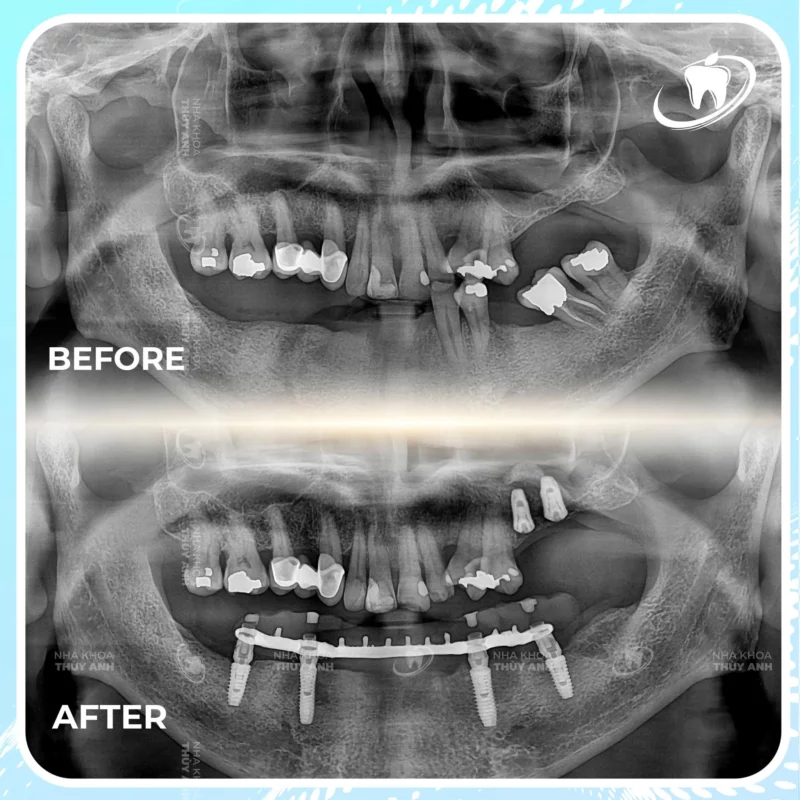

Tình trạng răng của chú Dũng khá phức tạp. Toàn bộ răng hàm dưới đã hư hỏng nặng, không thể giữ lại. Ở hàm trên, chú mất 2 răng số 6 và 7, khiến khả năng ăn nhai bị ảnh hưởng rõ rệt. Sau khi thăm khám và lập kế hoạch chi tiết, bác sĩ chỉ định: nhổ bỏ toàn bộ răng hư hỏng hàm dưới, cấy 4 trụ implant để phục hình hàm cố định toàn hàm dưới, đồng thời cấy thêm 2 trụ implant ở vị trí răng 6 và 7 hàm trên.

Toàn bộ quá trình được trực tiếp thực hiện bởi bác sĩ Nguyễn Thế Anh, với sự hỗ trợ của hệ thống máy móc hiện đại và quy trình kiểm soát chặt chẽ. Mỗi bước đều được tính toán kỹ lưỡng để đảm bảo độ chính xác và an toàn cao nhất cho chú.

Sau thời gian chờ implant tích hợp chắc chắn, chú Dũng đã được lắp hàm răng sứ cố định hoàn chỉnh. Đây là lúc hành trình làm răng chính thức khép lại. Hàm răng mới chắc chắn, ăn nhai tốt và nhìn rất tự nhiên. Khi nói chuyện hay cười, chú không còn cảm giác thiếu tự tin như trước nữa.